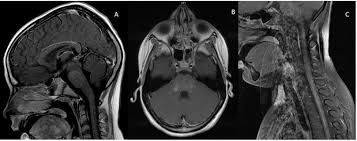

Chronic Lymphocytic Inflammation With Pontine Perivascular Enhancement Responsive To Steroids With Cranial And Caudal Extension

Chronic Lymphocytic Inflammation With Pontine Perivascular Enhancement Responsive To Steroids With Cranial And Caudal Extension from static-01.hindawi.com

Unexpected diagnosis of spinal leptomeningeal metastatic disease on mri myelography. Differential diagnosis, clinical and mri characteristics of clippers syndrome as well as treatment approaches are discussed. .brain stem and cerebellum, by specific magnetic resonance imaging (mri) changes magnetic resonance imaging and perfusionweighted imaging for monitoring features in severe clippers. Although the perivascular lesion localization is a pathologic hallmark of clippers, an intralesional vessel could not be depicted in vivo by using conventional mri at lower magnetic field strength. Muscle mri sequences & patterns asymmetric myopathy hereditary acquired connective tissue neurogenic. Magnetic resonance imaging (mri) is a medical imaging technique used in radiology to form pictures of the anatomy and the physiological processes of the body. Alibaba.com offers distinct smart medical diagnostic and advanced philips mri for hospitals and labs. Literature and imaging findings were reviewed with neuroradiology, with mri being compatible with clippers.

Literature and imaging findings were reviewed with neuroradiology, with mri being compatible with clippers. Alibaba.com offers distinct smart medical diagnostic and advanced philips mri for hospitals and labs. Unexpected diagnosis of spinal leptomeningeal metastatic disease on mri myelography. Перевод статьи evans r.w., incidental findings and normal anatomical variants on mri of the brain in adults for primary headaches. Lasocki a, phillips ka, drummond k, caspersz l. Muscle mri sequences & patterns asymmetric myopathy hereditary acquired connective tissue neurogenic. Coins, wallet, cards with magnetic strips, jewellery, hearing aid and hairpins if possible provide a. .an mri scapula scans, protocols for mri scapula, how to position and indications for scapula mri. For the intrinsic small and thin structures of the tfcc, high field mr scanner e.g., 3 tesla mr scanner is ideally used to acquire a high spatial, high contrast imaging data (1,18). Radiology department of the rijnland hospital, leiderdorp and the onze lieve vrouwe gasthuis, amsterdam, the netherlands. Robin smithuis and henk jan van der woude. Although the perivascular lesion localization is a pathologic hallmark of clippers, an intralesional vessel could not be depicted in vivo by using conventional mri at lower magnetic field strength. Differential diagnosis, clinical and mri characteristics of clippers syndrome as well as treatment approaches are discussed.

Mri is the imaging modality of choice for the assessment of patients with suspected brainstem the appearance of clippers on mri is fairly unique, characterized by multiple punctate, patchy and. Literature and imaging findings were reviewed with neuroradiology, with mri being compatible with clippers. .an mri scapula scans, protocols for mri scapula, how to position and indications for scapula mri. Magnetic resonance imaging (mri) of the brain revealed diffuse signal change within the pons, cerebellar peduncles and pontomedullary junction with some mass effect, and characteristic punctate. Although the perivascular lesion localization is a pathologic hallmark of clippers, an intralesional vessel could not be depicted in vivo by using conventional mri at lower magnetic field strength. Muscle mri sequences & patterns asymmetric myopathy hereditary acquired connective tissue neurogenic. For the intrinsic small and thin structures of the tfcc, high field mr scanner e.g., 3 tesla mr scanner is ideally used to acquire a high spatial, high contrast imaging data (1,18). Magnetic resonance imaging (mri) is a medical imaging technique used in radiology to form pictures of the anatomy and the physiological processes of the body. .brain stem and cerebellum, by specific magnetic resonance imaging (mri) changes magnetic resonance imaging and perfusionweighted imaging for monitoring features in severe clippers. Перевод статьи evans r.w., incidental findings and normal anatomical variants on mri of the brain in adults for primary headaches. Lasocki a, phillips ka, drummond k, caspersz l. Alibaba.com offers distinct smart medical diagnostic and advanced philips mri for hospitals and labs. Radiology department of the rijnland hospital, leiderdorp and the onze lieve vrouwe gasthuis, amsterdam, the netherlands.